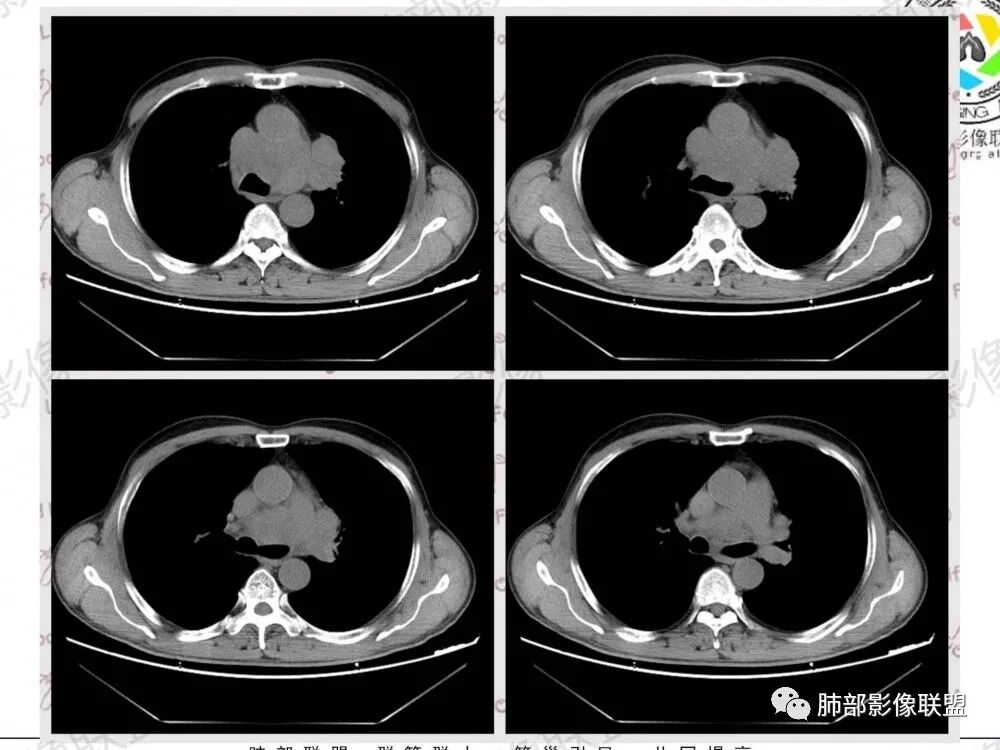

影像特点:

1.左肺门及纵隔见异常增大淋巴结,部分融合,不均匀轻度强化,未见明显坏死。

肿大淋巴结与纵隔血管等结构“无缝”贴合。

2.纵隔增宽但依旧居中。

1.这应当是常见的小细胞肺癌的转移方式。

别忘了,患者左肺上叶那个略显饱满的的小结节,有理由相信那是发源地。

因为这些符合肺癌的整个转移路径!

2、小细胞癌恶性程度高,发展迅速,转移发生早;常有纵隔淋巴结的明显增大融合(发生率达96.5%),呈“冰冻纵隔”,淋巴转移常为逐站的连续性转移;亦有血行转移,脑、肾上腺、肝、胰、骨髓等;转移灶常比原发灶大得多,即“娘小崽大”特点;